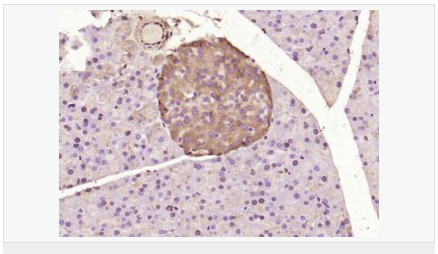

| 產(chǎn)品應(yīng)用 | WB=1:500-2000 ELISA=1:5000-10000 IHC-P=1:100-500 IHC-F=1:100-500 Flow-Cyt=1μg /test IF=1:100-500 (石蠟切片需做抗原修復(fù)) not yet tested in other applications. optimal dilutions/concentrations should be determined by the end user. |

| 細(xì)胞定位 | 細(xì)胞核 細(xì)胞漿 |

| 產(chǎn)品介紹 | ATF6 is a transcription factor that acts during endoplasmic reticulum stress by activating unfolded protein response target genes. It binds DNA on the 5'-CCAC[GA]-3'half of the ER stress response element (ERSE) (5'-CCAAT-N(9)-CCAC[GA]-3') and of ERSE II (5'-ATTGG-N-CCACG-3'). Binding to ERSE requires binding of NF-Y to ERSE. ATF6 could also be involved in activation of transcription by the serum response factor. ATF6 exists as a homodimer and heterodimer with ATF6 beta. The dimer interacts with the nuclear transcription factor Y (NF-Y) trimer through direct binding to NF-Y subunit C (NF-YC). It also interacts with the transcription factors GTF2I, YY1 and SRF. Under ER stress the cleaved N-terminal cytoplasmic domain translocates into the nucleus. The basic domain of ATF6 functions as a nuclear localization signal and the basic leucine zipper domain is sufficient for association with the NF-Y trimer and binding to ERSE. During the unfolded protein response an approximately 50 kDa fragment containing the cytoplasmic transcription factor domain is released by proteolysis. The cleavage seems to be performed sequentially by site 1 and site 2 proteases. ATF6 is N glycosylated, phosphorylated in vitro by MAPK14/P38MAPK and belongs to the bZIP family. Function: Transcription factor that acts during endoplasmic reticulum stress by activating unfolded protein response target genes. Binds DNA on the 5'-CCAC[GA]-3'half of the ER stress response element (ERSE) (5'-CCAAT-N(9)-CCAC[GA]-3') and of ERSE II (5'-ATTGG-N-CCACG-3'). Binding to ERSE requires binding of NF-Y to ERSE. Could also be involved in activation of transcription by the serum response factor. Subunit: Homodimer and heterodimer with ATF6-beta. The dimer interacts with the nuclear transcription factor Y (NF-Y) trimer through direct binding to NF-Y subunit C (NF-YC). Interacts also with the transcription factors GTF2I, YY1 and SRF. Subcellular Location: Endoplasmic reticulum membrane; Single-pass type II membrane protein. Processed cyclic AMP-dependent transcription factor ATF-6 alpha: Nucleus. Note=Under ER stress the cleaved N-terminal cytoplasmic domain translocates into the nucleus. Tissue Specificity: Ubiquitous. Post-translational modifications: During unfolded protein response an approximative 50 kDa fragment containing the cytoplasmic transcription factor domain is released by proteolysis. The cleavage seems to be performed sequentially by site-1 and site-2 proteases. N-glycosylated. The glycosylation status may serve as a sensor for ER homeostasis, resulting in ATF6 activation to trigger the unfolded protein response (UPR). Phosphorylated in vitro by MAPK14/P38MAPK. Similarity: Belongs to the bZIP family. ATF subfamily. Contains 1 bZIP (basic-leucine zipper) domain. SWISS: P18850 Gene ID: 22926 Database links: Entrez Gene: 22926 Human Entrez Gene: 226641 Mouse Omim: 605537 Human SwissProt: P18850 Human Unigene: 492740 Human Important Note: This product as supplied is intended for research use only, not for use in human, therapeutic or diagnostic applications. |